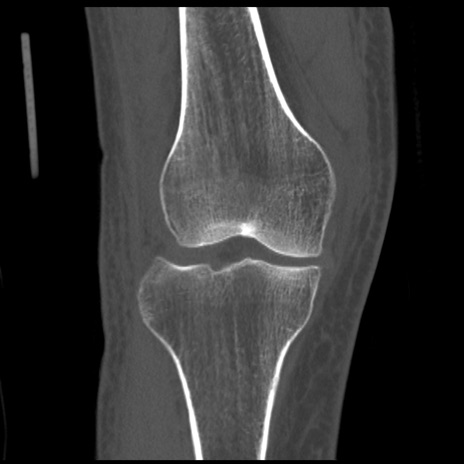

症例28 右膝関節CT(冠状断像)

右膝関節CT